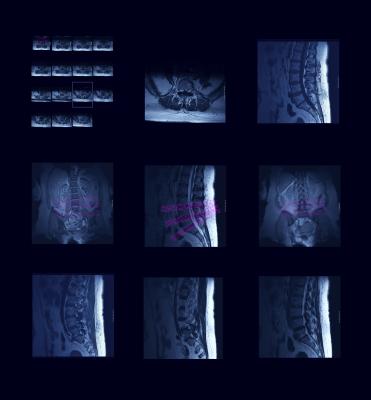

May 23, 2017 — Asterias Biotherapeutics Inc. recently announced new positive serial magnetic resonance imaging (MRI) data from its ongoing AST-OPC1 SCiStar Phase 1/2a clinical trial in patients with severe spinal cord injury.

- For the five AIS-A patients in the SCiStar study treated with 10 million AST-OPC1 cells (Cohort 2) who also received a serial MRI scan at six months of follow-up, the serial MRI scans indicated no sign of lesion cavities in any patient. These fluid-filled cavities typically form by about three months following severe spinal cord injury and prevent significant recovery of motor and sensory function;

- For the three patients in Cohort 2 that have also completed 12 months of follow-up, serial MRI scans at 12 months continued to indicate no signs of lesion cavities; and

- All three AIS-A patients who received a low dose of 2 million cells (Cohort 1) in the SCiStar study also showed no sign of lesion cavities in any patient through 1 year of follow-up. All three patients are continuing long-term follow-up and will receive additional MRI scans annually.

The MRI results are supportive of the extensive pre-clinical data on AST-OPC1 showing that the cells durably engraft and help prevent cavitation at the injury site. Cavitation is a destructive process that occurs within the spinal cord following spinal cord injuries, and typically results in permanent loss of motor and sensory function. Additionally, a patient with cavitation can develop a condition known as syringomyelia, which results in additional neurological and functional damage to the patient.

Under the study protocol, patients are monitored by MRI scans at regular intervals over 12 months in order to assess status of the injection site and surrounding tissues.